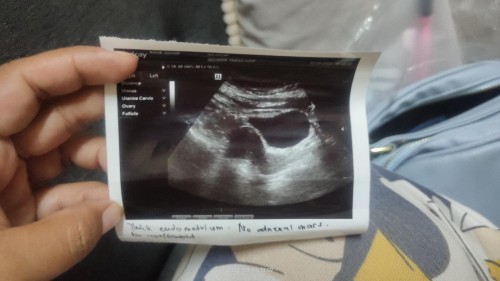

doktor cakap baru 4 minggu sebab tak nampak kantung..Sbb dinding rahim dah nampak menebal

Baca lagiDo not worry mommy ! You’re not alone ! ☺️ Sy pun ada bt ultrasound time 4weeks sbb misi minta sy bt ultrasound dlu sebelum buka buku . Masa kt klinik tu bt ultrasound mmg doktor cakap x nampak lg , tp rahim sdg mengembang ! 😍 Kita think positive , jaga kesihatan baik2 . Doktor pun ada bt repeat scan nnti , I can’t wait to see my baby ! 😍

Sama mcm sy sis. Sebelum pegi klinik dah test upt 2 kali, 2-2 +ve. Dr nampak kita mcm risau, dia suruh test upt lagi, alhamdulillah +ve. Dr bgtau rahim tebal, lagi 2 minggu dia suruh dtg balik..

saya masa scan 5w hanya nampak dinding rahim menebal.. 6w dah nmpak kantung..so skrg tunggu 10w baru repeat scan.. x sabar rasa..